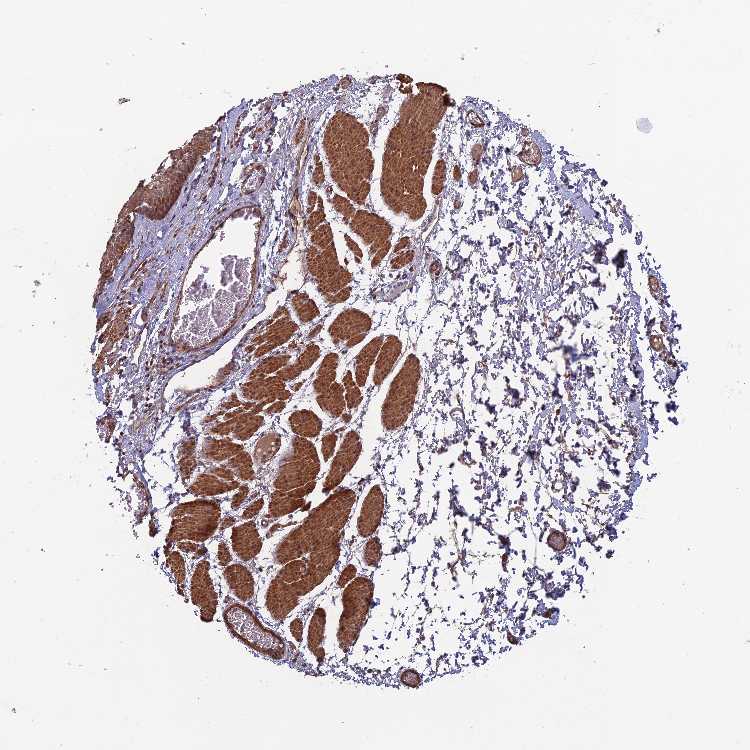

ESOPHAGUS - Antibody stainingi

Antibody staining in the annotated cell types in the current human tissue is reported as not detected, low, medium, or high, based on conventional immunohistochemistry profiling in selected tissues. This score is based on the combination of the staining intensity and fraction of stained cells.

Each image is clickable and will lead to virtual microscopy that enables deeper exploration of all samples and also displays staining intensity scores, fraction scores and subcellular localization as well as patient and tissue information for each sample.

Antibody HPA043812

Squamous epithelial cells Medium